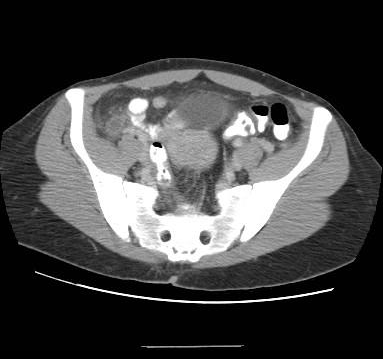

CT Abdomen/Pelvis (gold standard in adults)

• Sensitivity 94–98%, specificity 95–99%

• Findings:

• Appendiceal diameter >6 mm (thickened wall, lumen distension)

• Periappendiceal fat stranding

• Arrowhead sign (oral contrast funnel at cecal base pointing to occluded orifice)

• Appendicolith (calcified fecalith)

• Phlegmon or abscess in perforated cases

CT showing acute appendicitis — arrowhead sign, wall thickening, and periappendiceal fat stranding

Axial CT with IV/oral contrast: thickened appendix in the right iliac fossa with the arrowhead sign at the cecal base, circumferential wall enhancement, and periappendiceal fat stranding — hallmark findings of acute appendicitis.